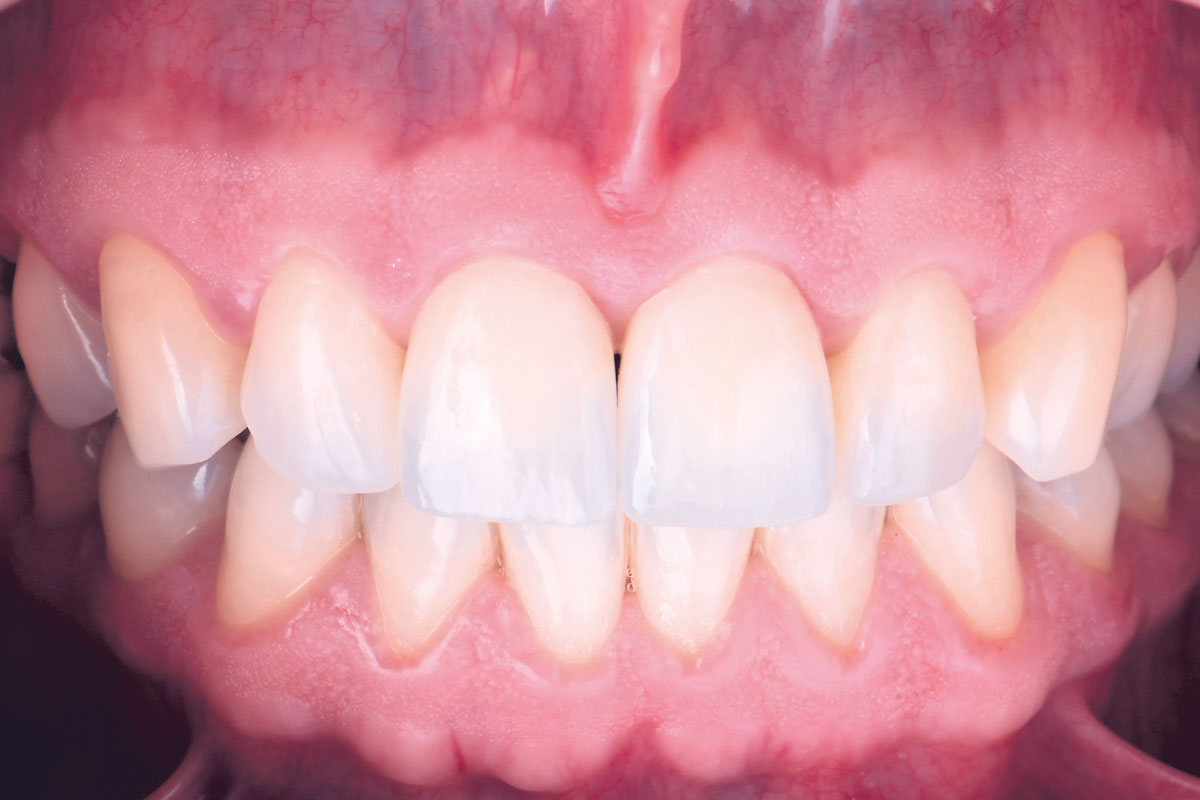

09/12 - Patient´s full smile with final ceramic crowns

Treatment of a double root fracture in the aesthetic zone with cerabone® – Dr. J. M. Abarca